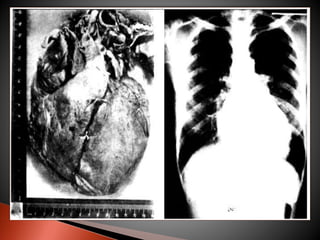

 FORMA CARDÍACA  é a mais importante

forma ao doente chagásico e a principal causa de

morte. Pode apresentar-se sem sintomatologia, mas

com alterações eletrocardiográficas, como uma

síndrome de insuficiência cardíaca progressiva,

insuficiência cardíaca fulminante, ou com arritimias

graves e morte súbita.

 SINAIS E SINTOMAS  palpitação,

dispnéia,edema,dor no peito, tosse, tonturas, e

desmaios.

 o Rx de torax revela cardiomegalia global discreta,

moderada ou acentuada.

 FORMA CARDÍACA é a mais importante forma ao doente chagásico e a principal causa de morte. Pode apresentar-se sem sintomatologia, mas com alterações eletrocardiográficas, como uma síndrome de insuficiência cardíaca progressiva, insuficiência cardíaca fulminante, ou com arritimias graves e morte súbita.  SINAIS E SINTOMAS  palpitação, dispnéia,edema,dor no peito, tosse, tonturas, e desmaios.  o Rx de torax revela cardiomegalia global discreta, moderada ou acentuada.